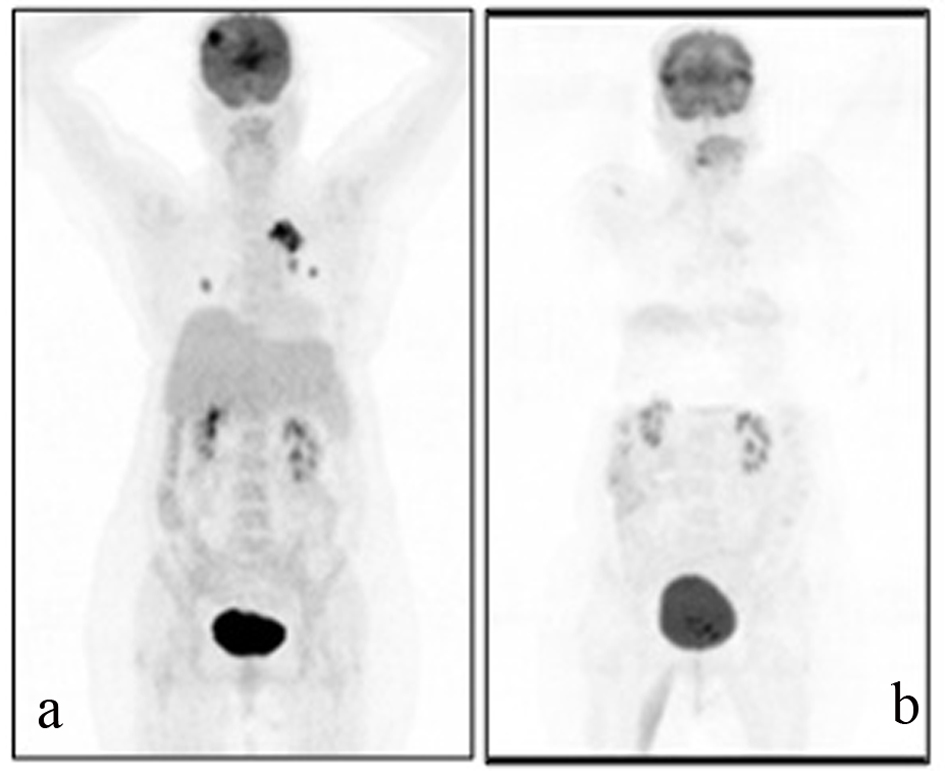

A 54-years-old female patient was diagnosed with grade 2 invasive ductal carcinoma of the breast in 1997. Modified radical mastectomy was performed to the patient who has spread disease to sentinel lymph nodes. Post-operative pathological examination revealed stage II breast cancer with two out of 14 lymph nodes positive (pN1), ER 3+, PR 3+, and CERB-B2 3+. Adjuvant radiotheraphy and chemotheraphy with 4 cycles anthracycline cyclophosphamide and 4 cycles docetaxel was performed and 5-year adjuvant treatment of tamoxifene was commenced. In 2005, recurrence appeared in lung and supraclavicular lymph nodes and she was treated for 6 cycles with trastuzumab and vinorelbine. Trastuzumab and vinorelbine were continued for two and a half years and there was no evidence of progression in this period. Lapatinib and capecitabine were commenced after progression that was observed on CT scan in lung lesions and 22 cycles of this treatment were performed. F-18 Fluorodeoxyglucose Positron Emmition Tomography (PET-CT), performed in order to confirm the extent of metastases of the patient whose CT imaging revealed lung lesions, revealed metastatic lesion in her lungs. Cranial MRI was performed to the patient who complained from headache and whose PET-CT imaging revealed cranial metastasis. Cranial radiotherapy (3 gy/day, total 30 gy) was performed to the patient for her frontal lobe lesions. Given her poor performance status (ECOG: 3) and hormone receptor positivity of primary tumor, palliative therapy and letrozole (2.5 mg/day) was started after the radiotherapy. Control PET-CT was performed after six months (Fig. 1a, b) and revealed near-complete response as a result that was obtained with the letrozole treatment.

![]() Click for large image | Figure 1. A 69-year-old female patient with a history of breast cancer underwent FDG PET/CT imaging before and after the therapy. For the first PET/CT imaging patient was intravenously injected 592 MBq (16 mCi) F-18 FDG after 6 hours of fasting period. Then one hour of waiting time in a silent room patient was imaged using an integrated PET/CT camera, which was consisted of a 6-slice CT gantry integrated on a LSO based full-ring PET scanner (Siements Biograph 6, IL, USA). Anterior-posterior maximum intensity projection (MIP) PET image (a) sowed intense hypermetabolic multiple nodular lesions in the right lung superior lobe with a maximum standard uptake value (SUV max) of 14.0 and left hilar hypermetabolic lymph node with a SUVmax of 6.4. In cranial slices intense hypermetabolic lesion in the right frontal lobe with a SUVmax of 13.5 was seen. Six months after the first PET/CT imaging this patient referred to Nuclear Medicine department for another PET/CT imaging after the therapy to evaluate the therapy response. Patient wan injected 418.1 MBq (11.3 mCi) F-18 FDG for imaging. Anterior and posterior MIP image (b) showed significant regression in the cranial, lung and left hilar lesions. |